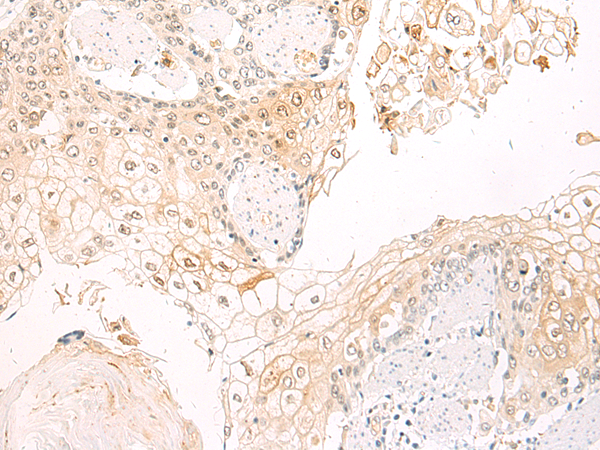

ELISA, IHC |

IHC positive control: |

Human esophagus cancer |

IHC Recommend dilution: |

50-100 |